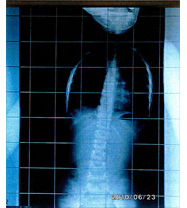

平成21年10月21日

装具して5度

レントゲン平成20年8月11日 レントゲン平成21年2月25日 レントゲン平成21年10月21日

平成22年2月17日 レントゲン検診装具なし7度に大改善   平成22年6月23日 レントゲン 平成22年11月24日 レントゲン

レントゲン平成22年2月17日 レントゲン平成22年6月23日 レントゲン平成22年11月24日

南院長より正常範囲と診断 南院長より連続して正常範囲と診断